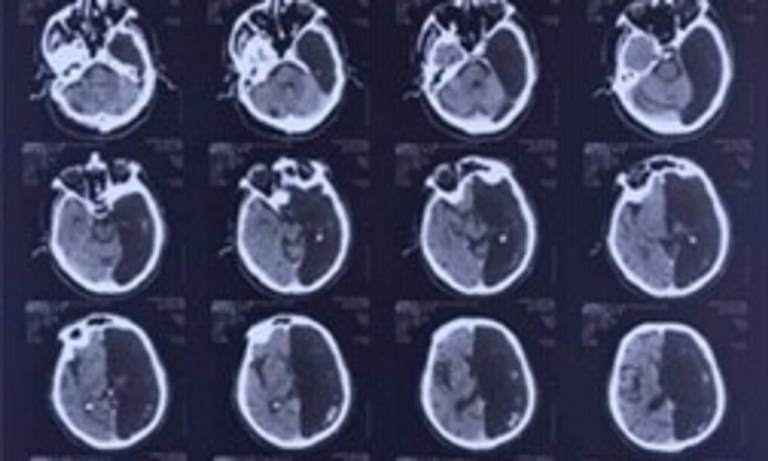

“Radiologists performed a computer tomography of his head and were puzzled for some time – the part of the brain of the retired man where the ischemia attack was supposed to have happened was not there at all.

“Instead of the left side of the brain there was a black “hole” in computer images.”

Doctors concluded that all his life the right hemisphere had performed all the functions of the brain. The right side is responsible for creative tasks and coordinates the left side of the body.